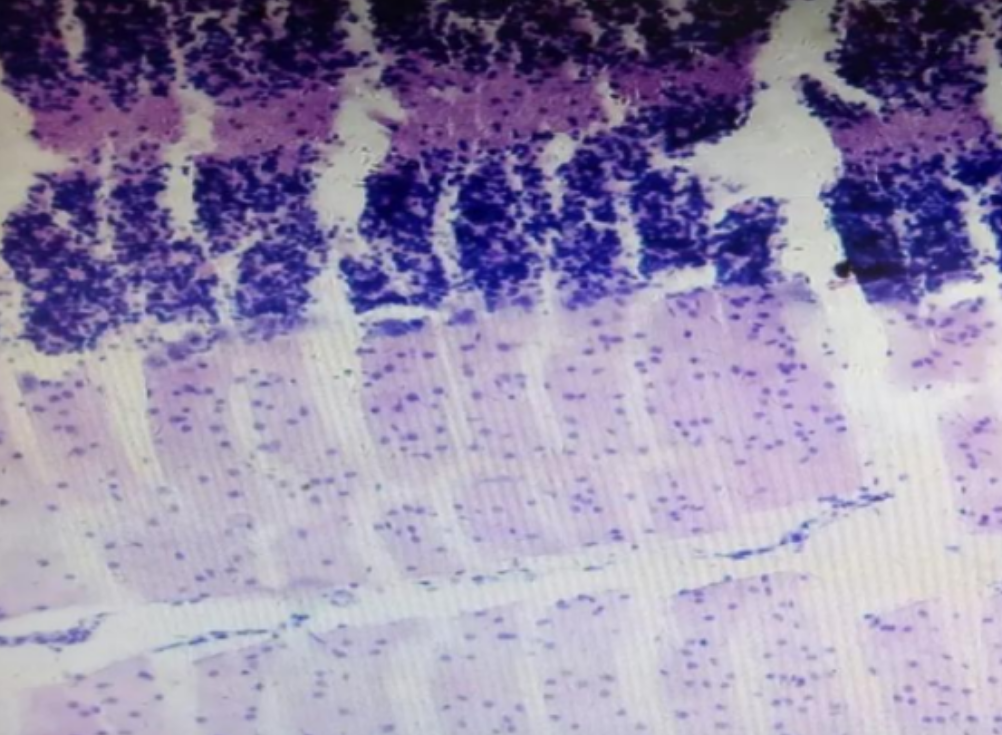

HE染色,全称苏木精-伊红染色法(Hematoxylin and Eosin staining),是最常见的组织切片染色技术之一,用于在显微镜下观察和分析组织或细胞的结构和形态。虽然HE染色是最常见且最基础的染色技术之一,😭但在实验过···

HE染色,全称苏木精-伊红染色法(Hematoxylin and Eosin staining),是最常见的组织切片染色技术之一,用于在显微镜下观察和分析组织或细胞的结构和形态。

虽然HE染色是最常见且最基础的染色技术之一,😭但在实验过程中,很容易出现各种情况导致染色切片质量参差不齐。所以,小编根据以往实验经验,给大家整理归纳出了15个HE染色中的常见问题,还包含问题原因分析以及解决方法哦~

形成原因:切片经梯度乙醇处理后没有完全脱水,导致二甲苯透明、中性树胶封固后残留大量水分。 解决方法:首先移去盖玻片,用二甲苯溶解封固剂如中性树胶,再将切片置入无水乙醇内,待切片重新脱水完全后,用二甲苯透明处理,中性树胶封固。要注意所有用于脱水和透明的液体,在使用一定时间后,应及时更换。 二、细胞核呈红、棕色 形成原因:苏木精染色液过度氧化,切片在苏木精染液染色后返蓝不足。 解决方法:每次染色之前检查苏木精染色液的染色能力,发现苏木精染色液氧化过度应及时更换。此外,切片经苏木精染色后,要给切片以足够的蓝化时间,蓝化过程可用流水、温水、弱碱性溶液(如稀氨水或0.2%碳酸氢钠)等处理。 三、切片在脱蜡后出现大片白色斑点 形成原因:由于烤(烘)片温度太低,切片上的组织蜡膜在脱蜡前没有充分烤(烘)融化。或是因为切片在二甲苯液中停留时间不足,或二甲苯使用过久,造成的脱蜡不彻底。 解决方法:若是由于切片烤(烘)温度低所致,可以先用二甲苯去除切片上的封固胶,然后重新用二甲苯脱去切片上的石蜡,再进行后续染色。若是由于切片在脱蜡的二甲苯中停留时间不足或脱蜡二甲苯使用过久浓度不足所致,则需将切片退回到二甲苯中,停留较长时间,或更换二甲苯液体重新脱蜡,再入乙醇重新脱二甲苯,入0.5%盐酸水溶液褪色后,重新HE染色。 四、细胞核苍白暗淡,即苏木精染色太淡 形成原因:切片在苏木精染色液停留时间太短;苏木精染色液过度氧化,失去染色能力,不能再继续使用;分化步骤处理时间过长;固定不及时。此外值得注意的是,若骨组织细胞核暗淡,大多是脱钙过度造成的。 解决方法:切片重新染色。如果组织在酸性固定液(如Zenker、Bouin)或非中性缓冲甲醛液固定时间过长,细胞核染色能力将减弱,需增加其在苏木精染色液的时间,或用一些方法增加组织的嗜碱性,以改善细胞核的着色。例如,上述组织玻片可以使用Weigert铁苏木精染色液。如果组织是用Zenker液固定的,可将切片脱蜡后放在5%碳酸氢钠溶液3~4h,流水冲洗5min后染色。如果组织是用Bouin液固定的,可将切片脱蜡后放在5%碳酸锂1h,流水冲洗10min后染色。 五、细胞核过染,苏木精染液占据了细胞质 形成原因:玻片在苏木精染色液停留时间过长,或是切片太厚、分化步骤时间太短。 解决方法:如果不是因为切片太厚(用显微镜仔细上下微调,只有一二层细胞核层次),就需将切片进行脱色、漂白、重新染色,适当调整染色和分化时间。但如果确定是由于切片太厚导致的细胞核过染,则需要重新切片。 六、伊红着色淡 形成原因:可能是伊红染液pH值大于5,也可能是蓝化液残留过多,切片太薄,或是切片经伊红染色后在乙醇脱水时间过长。 解决方法:检查伊红染液pH值,必要的话,用乙酸将其调节在4.6~5.0之间,从而使伊红染色色彩艳丽。此外,确保每次蓝化步骤完成后,使用的弱碱性溶液被充分洗去,玻片上没有残留的弱碱性溶液。最后,检查切片的厚度,且脱水时不要让切片在低浓度乙醇中停留时间过长,因为含水多的低浓度乙醇会将切片伊红的颜色分化掉。 七、细胞质过染、分色不足 形成原因:伊红染色液浓度太高,特别是存在焰红燃料、四溴四氯荧光素钠。切片在伊红染色时间过长,或是切片在伊红染色后经乙醇脱水步骤时时间太短,而使乙醇分化伊红的作用不能产生,都能够使细胞质过染。 解决方法:适当稀释伊红染色液,减少伊红染色时间,或使切片在乙醇脱水等步骤时,停留时间相对均匀。同样,也要检查切片的厚度是否合适。 八、切片中出现蓝黑色沉淀物 形成原因:苏木精染色液中的金属膜黏附在玻片上。 解决方法:染色前仔细过滤苏木精染色液,建议使用半氧化苏木精染色液,如Gill苏木精染色液,可以避免过多的金属膜产生。 九、光镜下切片某些区域难以聚焦 形成原因:盖玻片上可能有封固切片的封固剂。 解决方法:移去盖玻片,重新用干净的盖玻片封片。检查切片封片方法,是人工手工封法,还是机器自动封法,如有问题及时调整。 十、封固剂从盖玻片与载玻片之间的缝隙回缩 形成原因:盖玻片弯曲或不平整,或是封固剂含二甲苯过多,稀释过度。 解决方法:移去盖玻片,重新找一张盖玻片,用干净的封固剂封片。如用手工封片法,保证在封固结束时,封固剂容器盖子为紧闭状态。且尽量使用小的容器盛装封固剂,一旦封固剂太黏稠,就可以选择废弃。 十一、细胞核呈灰蓝状态 形成原因:可能由于组织处理温度过高、过热,在液体石蜡中停留的时间过长。或是固定时间太短后,直接在高浓度的乙醇中进行了脱水处理。 解决方法:理论上来说,仅在组织浸蜡步骤才进行加热,组织不能在热蜡液中停留太久。如果由于某些原因不能进行下一步包埋处理,可将组织连同塑料包埋盒一并放置在室温空气中,冷却凝固,以备包埋。待需要包埋时再重新加温直至石蜡融化即可。组织在处理前必须确保固定良好,脱水最好能从低浓度的乙醇开始。 十二、类色素的点状结晶和黑色光滑细胞核 形成原因:这种裸核改变是因为切片封片前放置在空气中的时间太长,以至于二甲苯挥发,切片干燥。 解决方法:移去组织切片上的盖玻片和封固剂,重新处理。将切片水洗数分钟,然后重新脱水、透明、封固。封片过程中要保持组织切片的轻度湿润,尽量不要让其干燥。 十三、染色过淡或过浓 解决方法:如果染色过淡,可以增加染色剂的浓度、延长染色时间或更换新鲜的染色剂;如果染色过浓,则应减少染色剂的浓度或缩短染色时间。 十四、切片出现叠加褶皱 形成原因:新购买的玻片洁净度不够、用镊子撑开切片时操作不够熟练未能平整伸展,或玻片表面有油脂,切片粘贴不牢。另外,烤片时间不足、烤片温度过低或切片过厚造成切片脱落,都会造成重叠或有皱褶的情况。 解决方法:新购买的玻片最好能用硫酸清洁液浸泡一晚,然后流水冲洗干净。在适宜的温度下烤片时间宁长勿短,保证有充足的烤片时间和温度。另外,切片刀要锋利,才能切出厚薄适宜的切片,保证切片不会因为过厚而脱落。 十五、组织残缺不全或有刮划痕迹 形成原因:组织残缺不全是由于切片时修整蜡块时深度不够、组织没有全部暴露于切面。切片的刮划痕迹是由于切片刀的刀锋有缺口、包埋的组织有异物,或是钙化组织、骨组织及包埋石蜡有沙粒造成的。 解决方法:修整蜡块时保证组织块全部暴露于切面,切片时保证切片刀的锋利没刀口。同时在组织取材时去除手术异物和钙化组织。最后,骨组织要完全脱钙,这样可以保证切片的完整和平整美观。 *注:由于实验中导致结果出现误差的原因多种多样,以上内容仅供参考,具体根据实际情况进行判断。